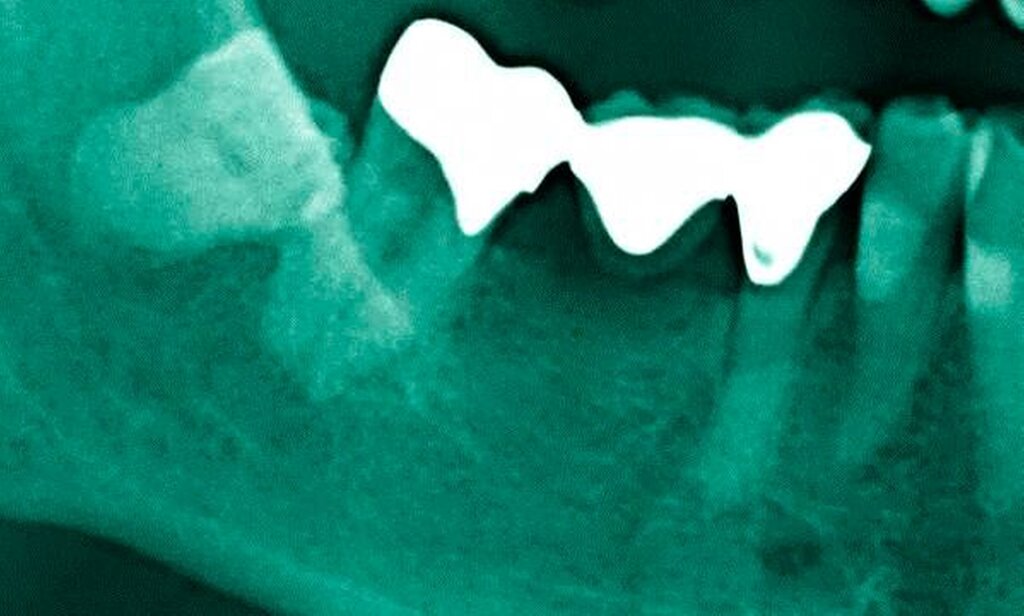

Abbildung 3: ausgedehnte Kronen- und Wurzelkaries unter einer Krone am Pfeilerzahn 47 einer seit Jahrzehnten eingegliederten Brücke von 45–47 bei einer 71-jährigen Patientin, die nach einer zerebrovaskulären Erkrankung unter Antikoagulantientherapie steht, vor etwa zwei Jahren hat sie eine Umstellung auf eine fluoridfreie Zahnpaste vorgenommen.

3. Restaurative Versorgungen bei Wurzelkaries

Freiliegende Wurzeloberflächen können im Alter ein locus minoris resistentiae für Karies sein. Im Zusammenspiel ungünstiger Ernährungsgewohnheiten, nachlassender Mundhygiene sowie Änderungen von Speichelquantität und -qualität kommt es zuweilen zu einem präventiv und restaurativ schwer beherrschbaren Auftreten von Wurzelkaries. Gut zugängliche Kariesläsionen können mit einphasig eingebrachtem Komposit (R1-Restaurationen) angegangen werden (Abbildungen 3 bis 5). Bei schwerer zugänglichen Arealen kommt ein zweiphasiges Vorgehen in Betracht (R2-Restaurationen). Das Vorgehen bei der R1- und bei der R2-Technik wurde mehrfach beschrieben [Frese et al., 2014a, b, c, d; Staehle et al., 2014, 2017]. Im Fall von zirkulärer Wurzelkaries sollte frühzeitig eingegriffen werden, da ansonsten die gesamte Zahnkrone frakturieren kann.